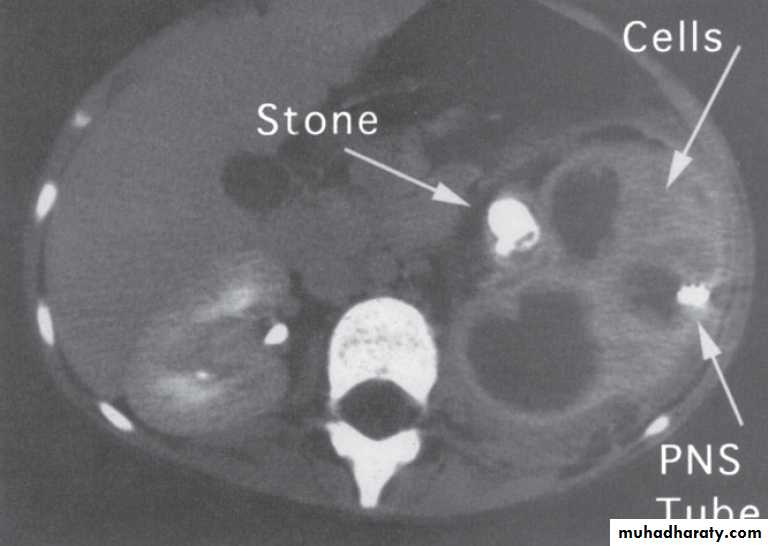

What's This Procedure?PCN= percutaneous nephrostomy for staghorn and kidney stone